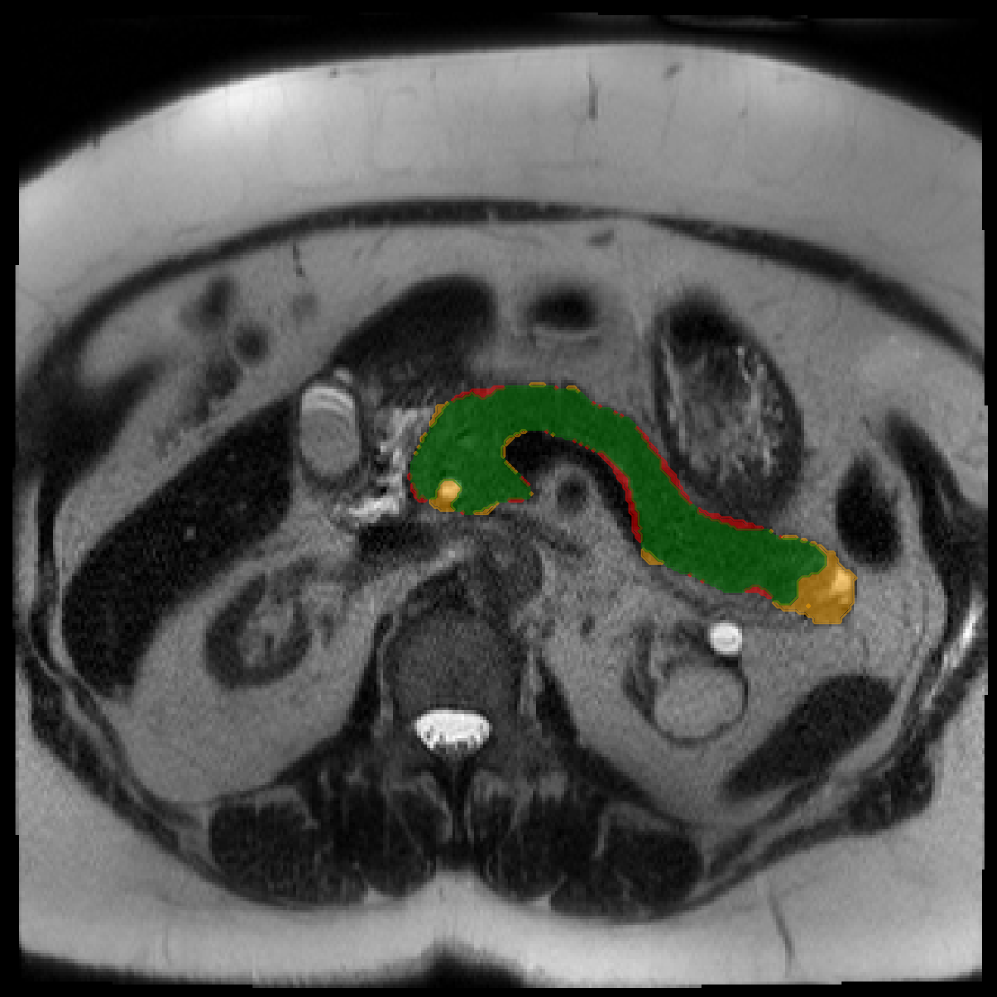

Each patient was categorized into one of these three ground truth classes: no risk/control, IPMN low-risk, or IPMN high-risk. To evaluate variability in image acquisition, we applied uniform manifold approximation and projection (UMAP) to image quality indicators, revealing distinct clustering patterns by imaging center and slice thickness. This heterogeneity reflects real-world clinical variability, enhancing the dataset’s generalizability while presenting technical challenges for model development. Fig. 6 shows examples of low-grade, high-grade, and cancer developing IPMNs from the Cyst-X dataset.

Accurate pancreas segmentation is a critical prerequisite for precise cyst analysis and classification. Recently, we developed PanSegNet [zhang2025large], a novel segmentation architecture incorporating linear self-attention layers [zhang2022dynamic] within the nnUNet framework [isensee2021nnu] to enhance global information modeling capabilities while maintaining computational efficiency (Fig. 1). PanSegNet demonstrated exceptional segmentation performance across both T1W and T2W modalities, achieving mean dice scores of 86.817.30% and 89.626.38%, respectively (Table 1, Fig. 2b-c). This performance significantly exceeded that of Swin-UNETR [hatamizadeh2021swin], one of the most used state-of-the-art transformer-based medical segmentation models, which achieved dice scores of 79.091.40% and 76.290.66% for T1W and T2W, respectively (). In this study, we integrated PanSegNet into our Cyst-X engine along with a classifier for risk prediction. In Section 2.2, we show that the choice of segmentation model affects the classification results. The performance advantage of PanSegNet was consistent across all seven medical centers, demonstrating robust generalization despite variations in imaging protocols and equipment (Table 1). This cross-institutional reliability is particularly important for clinical applications, where model performance must remain consistent regardless of imaging site or acquisition parameters.

2.2.1 Importance of accurate pancreas segmentation in classification

To assess the importance of accurate pancreas segmentation in classification, we evaluated how different ROI sources affect DenseNet-121’s performance. Specifically, we compared classification results using ROIs generated by PanSegNet and Swin-UNETR, both under centralized learning, against a baseline using radiologist-defined ROIs. As shown in Table 2, using PanSegNet’s masks resulted in only a modest performance decline, reflecting its strong segmentation quality. In contrast, Swin-UNETR led to a more substantial drop, demonstrating that inferior segmentation can directly compromise classification. For 3-class classification, the mean AUC dropped from 75.59% (radiologist ROI) to 72.26% with PanSegNet, and further to 66.95% with Swin-UNETR on T1-weighted images. On T2-weighted scans, the AUC declined from 81.09% to 74.18% (PanSegNet) and to 69.63% (Swin-UNETR). A similar trend was observed in 2-class classification: on T1W, AUC dropped from 78.13% to 74.84% (PanSegNet) and 70.20% (Swin-UNETR); on T2W, from 82.37% to 77.01% and 68.92%, respectively. These results emphasize that accurate segmentation—particularly via PanSegNet—is not only essential for volume estimation but also critical to preserving downstream classification performance in the Cyst-X pipeline.